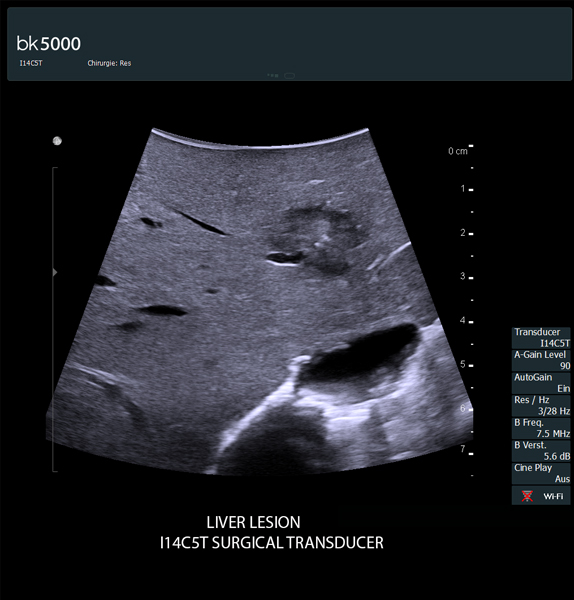

Ultrasound can advance intraoperative surgical procedures by helping you navigate and identify lesions and anatomical structures in real-time. This is particularly important as the data obtained from a preoperative CT or MRI scan can be outdated at the time of surgery.

The bk5000 surgical system provides the highest quality images that allow you to clearly see the margins of a lesion and to determine the best course of action. Using advanced graphics processing technology, this powerful system provides immediate, auto-optimized images that allow you to see the information you need, faster.